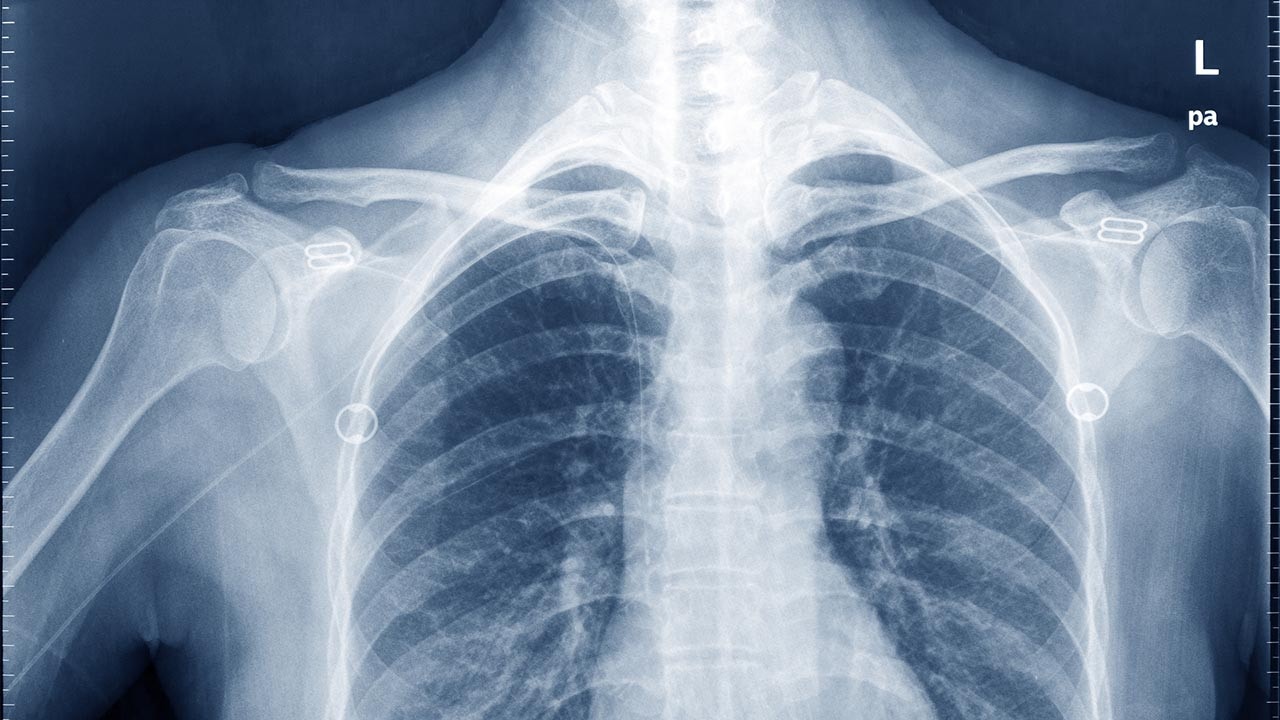

“With their educational background, chiropractors are especially well-equipped to work with individuals with scoliosis,” Dr. Gushaty says. “They can assess and safely treat people with scoliosis. They can also monitor the scoliosis, order x-rays and refer patients directly to a medical specialist when necessary.”